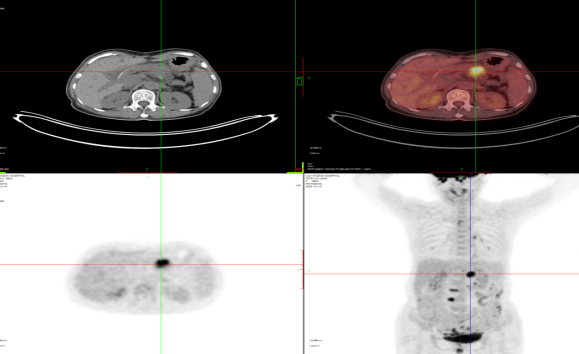

肺癌治疗后对比2022-3-18 2022-8-9